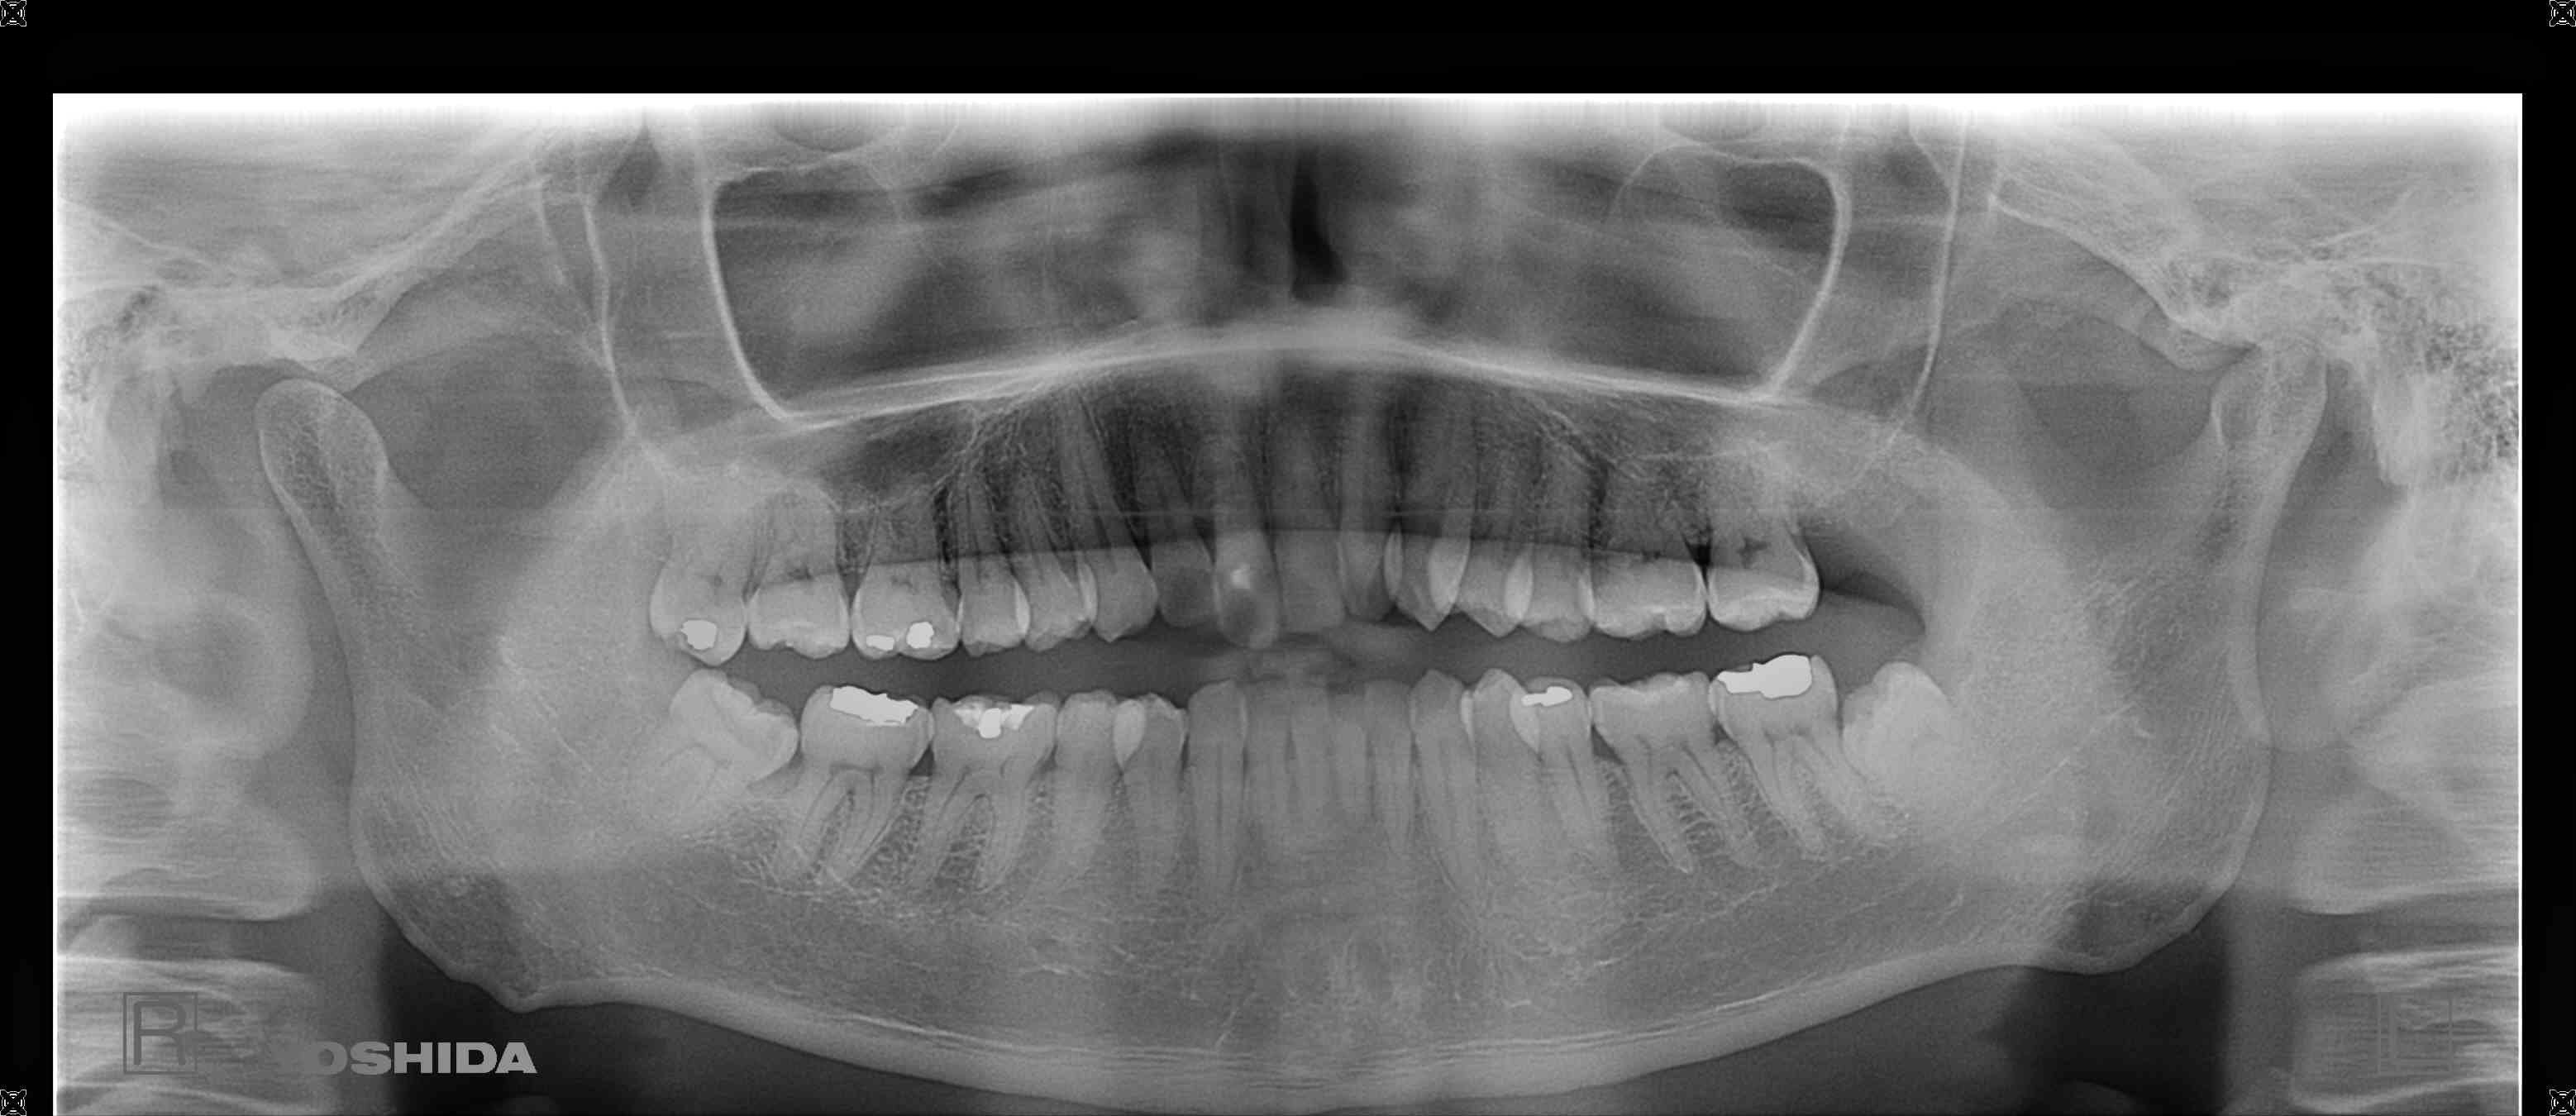

初診時、右上前歯がグラグラしており、抜歯およびインプラント治療をご希望されました。診査の結果、歯根が骨にほとんど埋まっておらず、保存は困難であったため、抜歯を行いました。

【レントゲン写真】